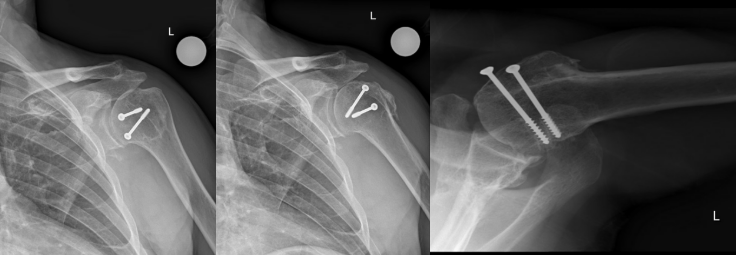

He was most recently evaluated at 13-years after the procedure. The patient reported high satisfaction and independent function, with only mild pain at maximal cross-body adduction. Examination showed a well-healed incision, active forward elevation to 170°, external rotation to 40°, and internal rotation to the lumbosacral junction with full strength of the deltoid and rotator cuff. Radiographs demonstrated a well-healed humeral head allograft, mild glenohumeral degenerative changes, a maintained subacromial space, and a centered humeral head on both anteroposterior and axillary views (Figure 4).